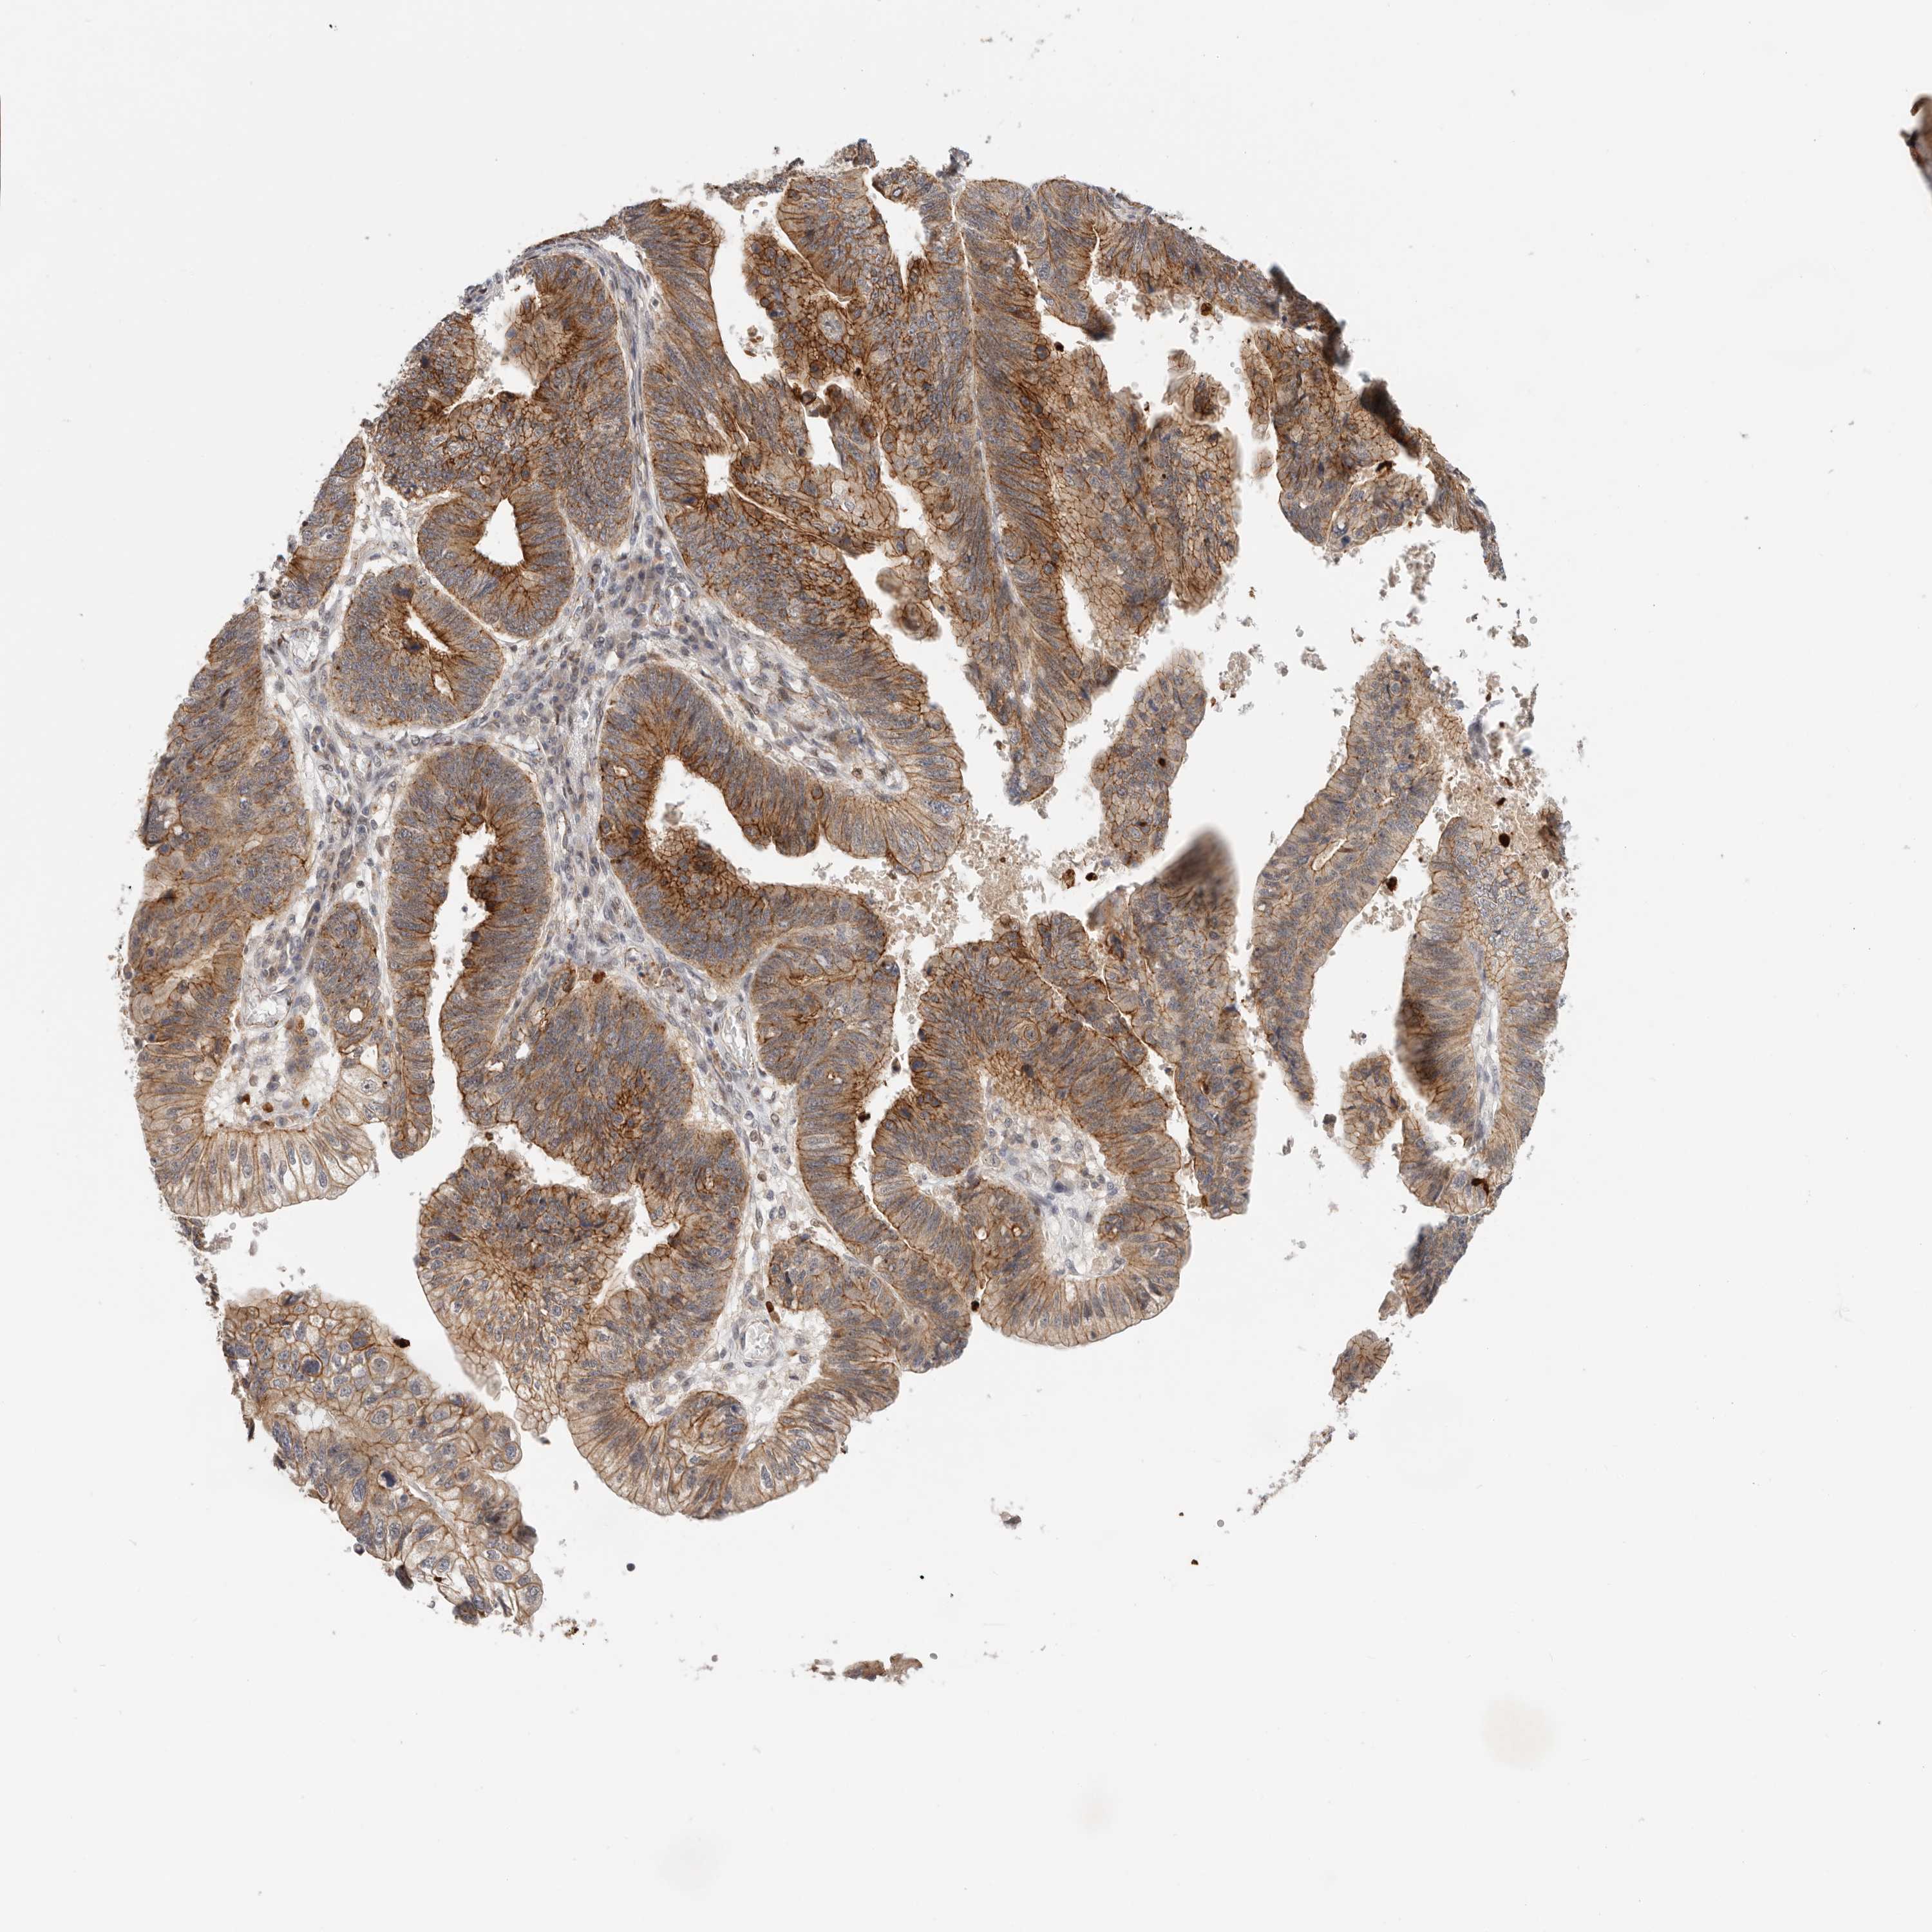

STOMACH CANCER - Protein expressioni

A mouse-over function shows sample information and annotation data. Click on an image to view it in a full screen mode. Samples can be filtered based on level of antibody staining by selecting one or several of the following categories: high, medium, low and not detected. The assay and annotation is described here.

Note that samples used for immunohistochemistry by the Human Protein Atlas do not correspond to samples in the TCGA dataset.

Antibody stainingi

Antibody staining in the annotated cell types in the current human tissue is reported as not detected, low, medium, or high, based on conventional immunohistochemistry profiling in selected tissues. This score is based on the combination of the staining intensity and fraction of stained cells.

Each image is clickable and will lead to virtual microscopy that enables deeper exploration of all samples and also displays staining intensity scores, fraction scores and subcellular localization as well as patient and tissue information for each sample.

HPA030212

HPA030213

HPA030214

HPA030215

CAB013496

Adenocarcinoma, NOS